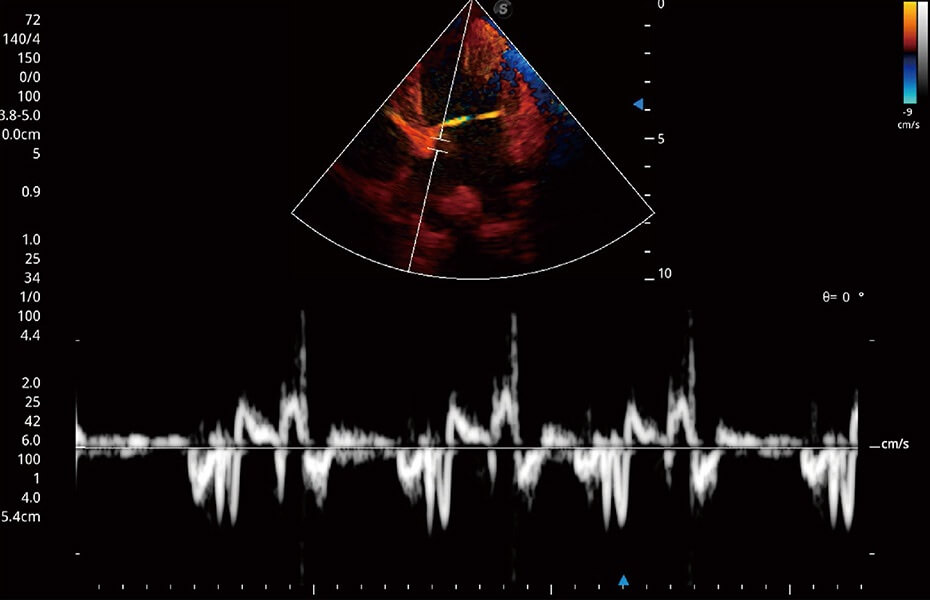

ProPet 60 作为一款高端台式动物超声设备,为动物医生的日常诊断提供了一系列贴合动物临床需求、解决临床实际问题的高级成像功能。凭借全系列高清探头,满足医生对腹部、心脏、生殖、浅表、肌骨等成像的所有需求,切实帮助您提升检查效率,提高诊断信心。

兽用彩色多普勒超声诊断系统